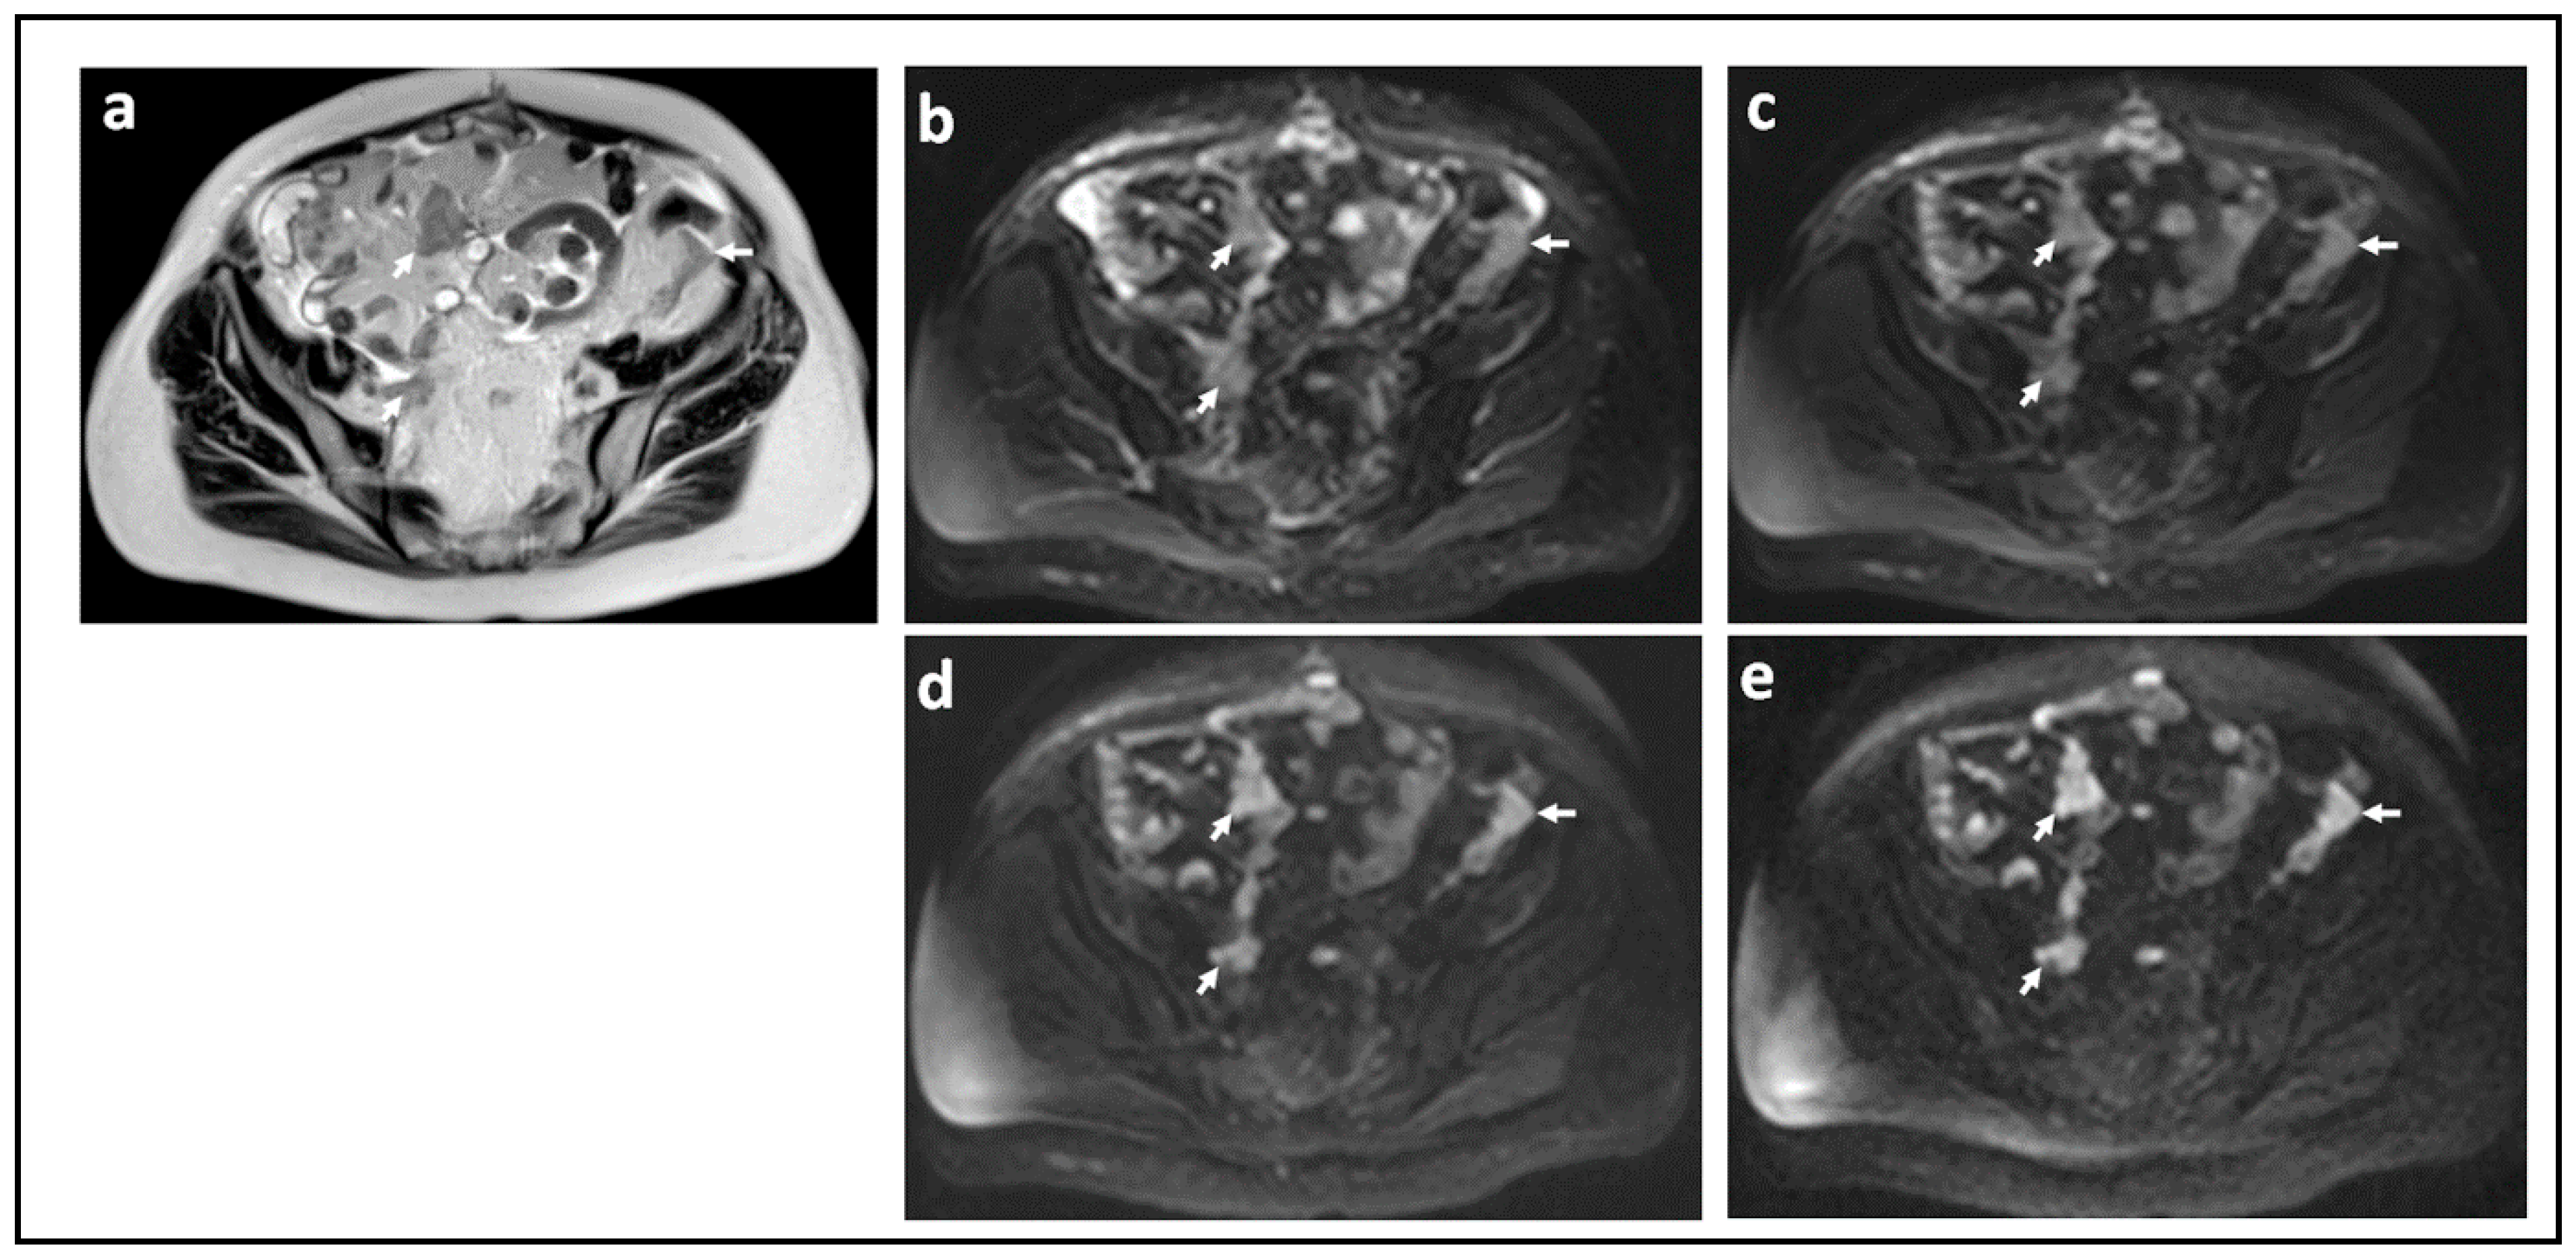

Figure 1.

Peritoneal metastases in high grade serous ovarian cancer showing increasing lesion conspicuity with increasing b-value: T2-W (a) and DW-MRI at b-values of 0 s/mm2 (b), 100 s/mm2 (c), 500 s/mm2 (d), and 900 s/mm2 (e). The irregular metastatic deposits on the surface of the bowel and in the mesentery (arrows) show diffusion restriction. They increase in conspicuity and contrast as diffusion weighting increases because they retain signal while signal from adjacent normal tissues diffuses away.